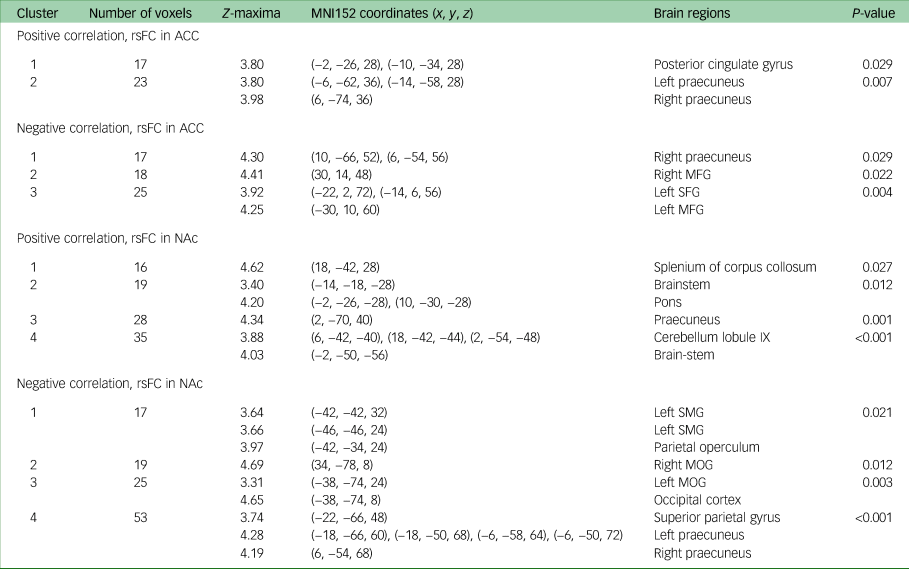

Seed-based correlation analysis: rsFC association with anhedonia change (week 8 to week 16)

There was a positive correlation between change in DARS score from week 8 to week 16 and week 8 rsFC between the ACC (which was used as the seed) and the posterior cingulate cortex (PCC) (P = 0.03), as well as the bilateral ventral-posterior praecuneus (P = 0.01) at week 8. Change in DARS score was also negatively correlated with week 8 rsFC between the ACC and right dorsal-anterior praecuneus (P = 0.03), middle frontal gyrus (left: P = 0.004; right: P = 0.02) and left superior frontal gyrus (P = 0.004).

Change in DARS score from week 8 to week 16 was also positively correlated with week 8 rsFC between the NAc (which was used as the seed) and bilateral ventral-posterior praecuneus (P = 0.001), cerebellum lobule IX (P < 0.001), pons (P = 0.01) and splenium of the corpus collosum (P = 0.03). Change in DARS score was negatively correlated with week 8 rsFC between the NAc and left supramarginal gyrus (P = 0.02), parietal operculum (P = 0.02), middle occipital gyrus (left: P = 0.004; right: P = 0.01), superior parietal gyrus (P < 0.001) and bilateral dorsal-anterior praecuneus (P < 0.001). All results are presented in Table 2, and presented visually in Fig. 1.

Table 2 MNI152 coordinates of Z-maxima for association between DARS score change and rsFC, week 8 to week 16a

MNI, Montreal Neurological Institute; DARS, Dimensional Anhedonia Rating Scale; rsFC, resting-state functional connectivity; ACC, anterior cingulate cortex; MFG, middle frontal gyrus; SFG, superior frontal gyrus; NAc, nucleus accumbens; SMG, supramarginal gyrus; MOG, middle occipital gyrus.

a. Controlled for Montgomery–Åsberg Depression Rating Scale score, gender and age.